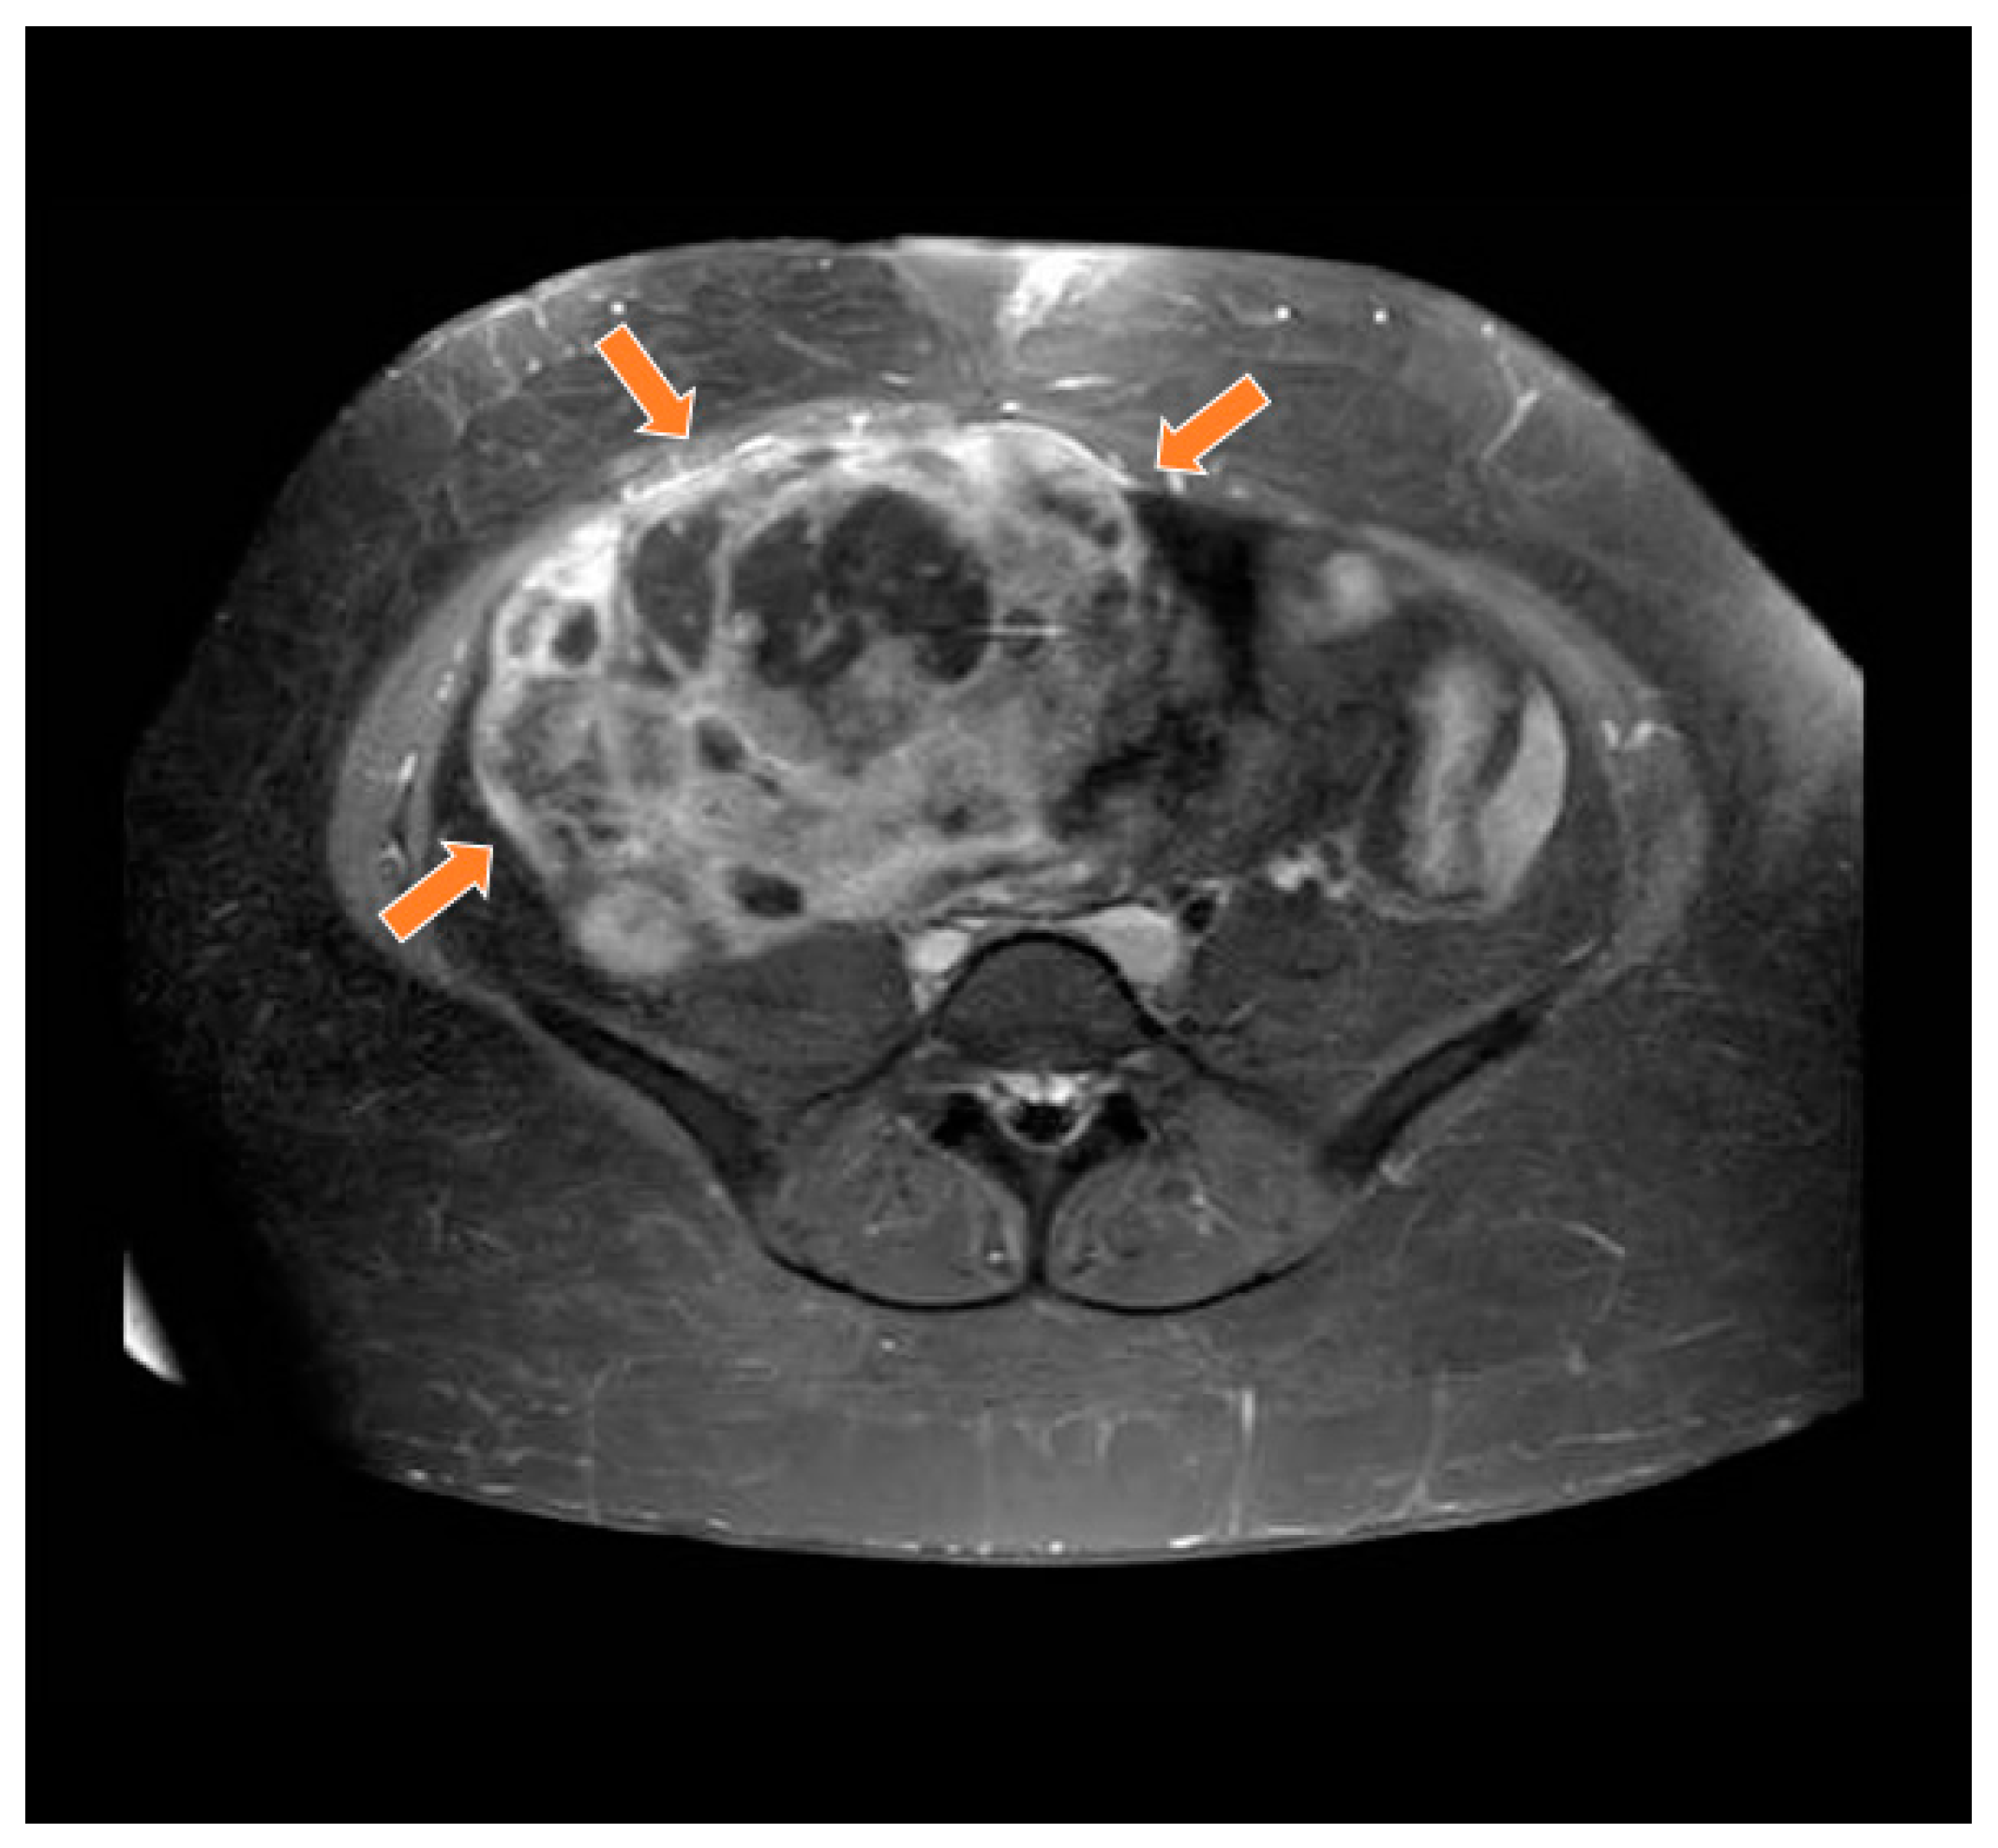

2. Case Report